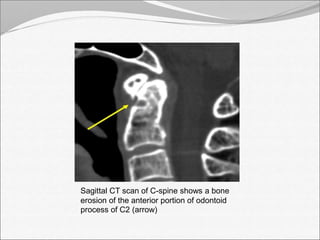

Sagittal CT scan of C-spine shows a bone

erosion of the anterior portion of odontoid

process of C2 (arrow)

• 25.

Sagittal CT scanof C-spine shows a bone erosion of the anterior portion of odontoid process of C2 (arrow)